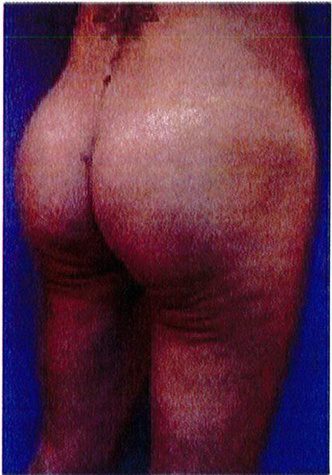

Hình. 19. . (A) Hình anh trước và (B) và sau phẫu thuật làm đầy mông của bệnh nhân chùng da vùng mông tương đối nhiều. Bệnh nhân được đặt khối implant dưới cân thể tích 330 mL ở hai bên.

Bệnh nhân 52 tuổi xuất hiện chùng da vùng mông (mức độ nặng), mong muốn giải quyết vấn đề này đồng thời tăng kích thước vòng ba. Hai khối anatomic implant

thể tích 330mL dạng silicone được đặt ở dưới cân cơ mông lớn.Hậu phẫu đánh giá thấy giảm thời gian hồi phục (Hình 19).